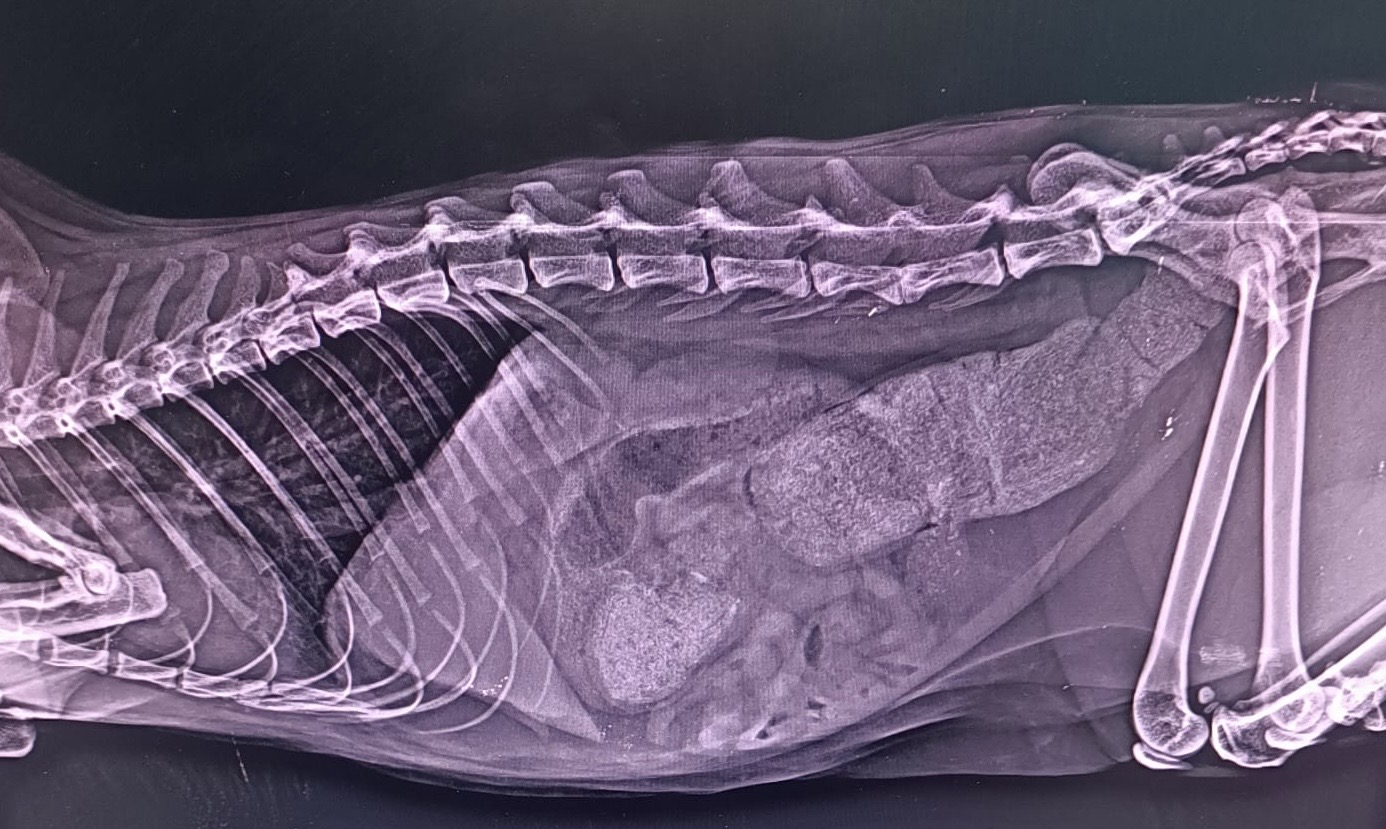

Radiología